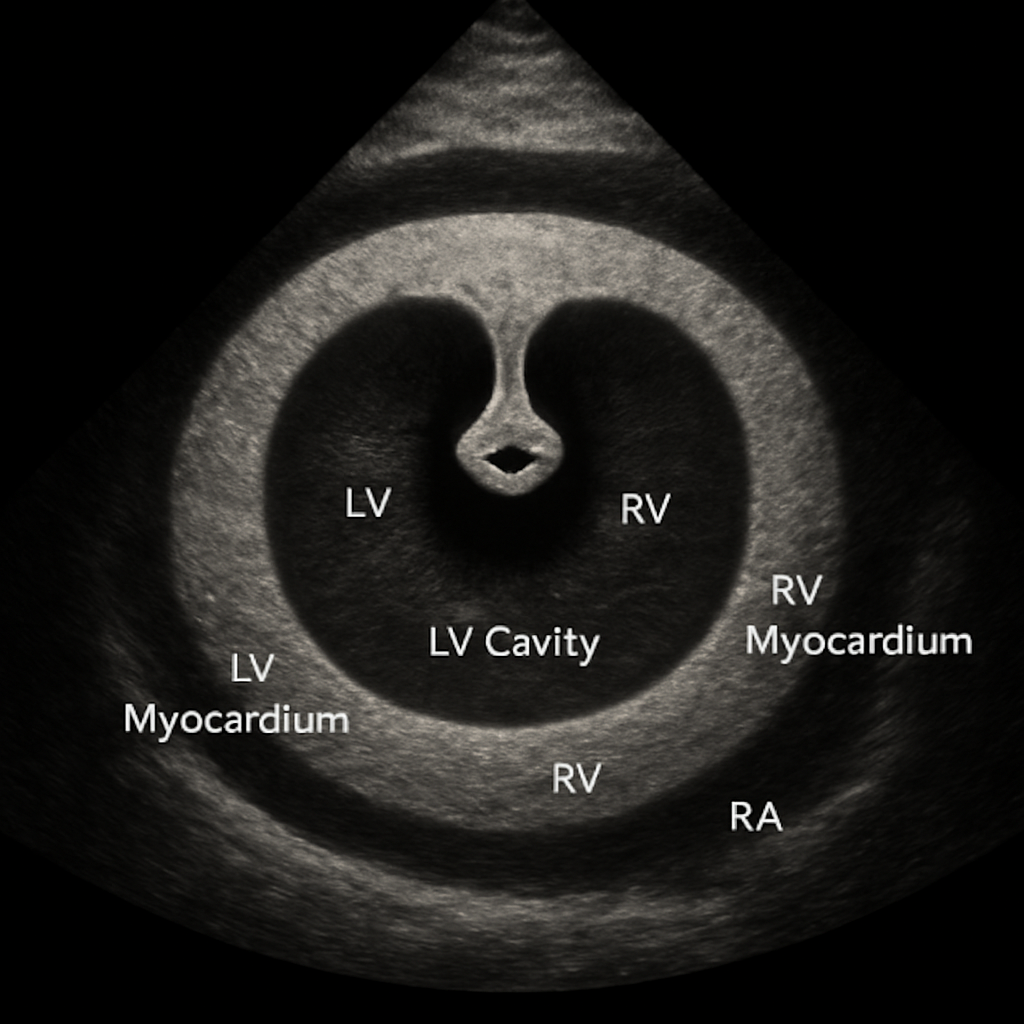

Echo — Parasternal Short Axis (Mitral Level)

Transthoracic echocardiogram parasternal short-axis (PSAX) view at the mitral valve level showing the fish-mouth appearance of the mitral valve, circular LV, and RV.

ULTRASOUND AI Generated 2026-03-16

Psax Mitral

2D B-mode TTE, PSAX at mitral valve level. Fish-mouth MV opening in circular LV cross-section.